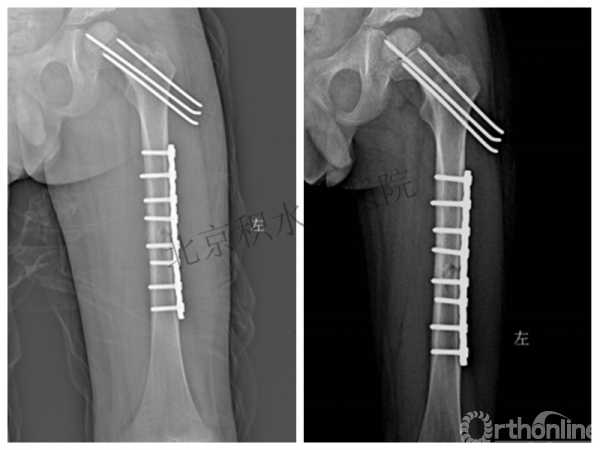

术后2年→再骨折→再次手术

钢板固定后一年

取板后再骨折→TEN

TEN取出后2个月

闭合复位再固定加尾帽